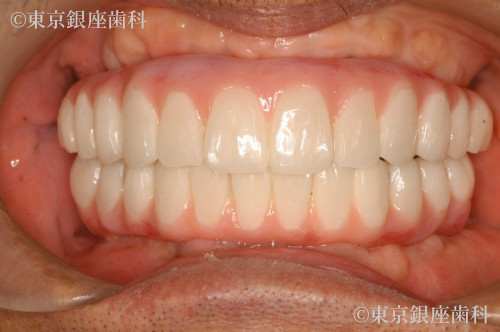

高額見積もりからセカンドオピニオンで最適治療を選択し噛める機能を獲得した80歳代男性の症例

After

施術内容 ワンデイインプラント

他院で1500万円超の提案を受け不安になり当院受診。精密診断の結果、片顎4本で十分と判断し上下ワンデイを実施。禁煙にも成功し現在も安定。

上下ワンデイインプラント